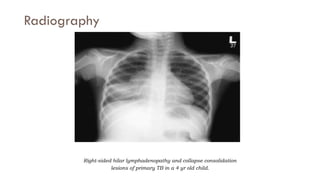

Radiography

Right-sided hilar lymphadenopathy and collapse consolidation

lesions of primary TB in a 4 yr old child.